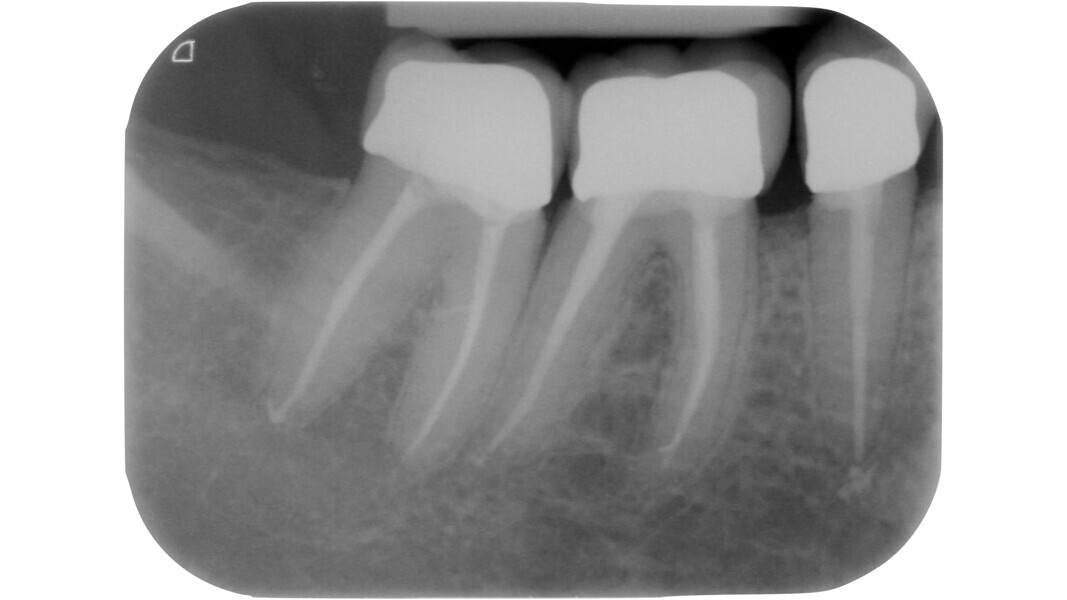

Fig. 8: Pre-op radiograph showing severe carious processes affecting teeth #45 and 46.

Fig. 11: Teeth #45 and 46 shaped and cleaned, ready for obturation of the root canal system.

Fig. 12: Radiograph after definitive restoration of the mandibular right quadrant.